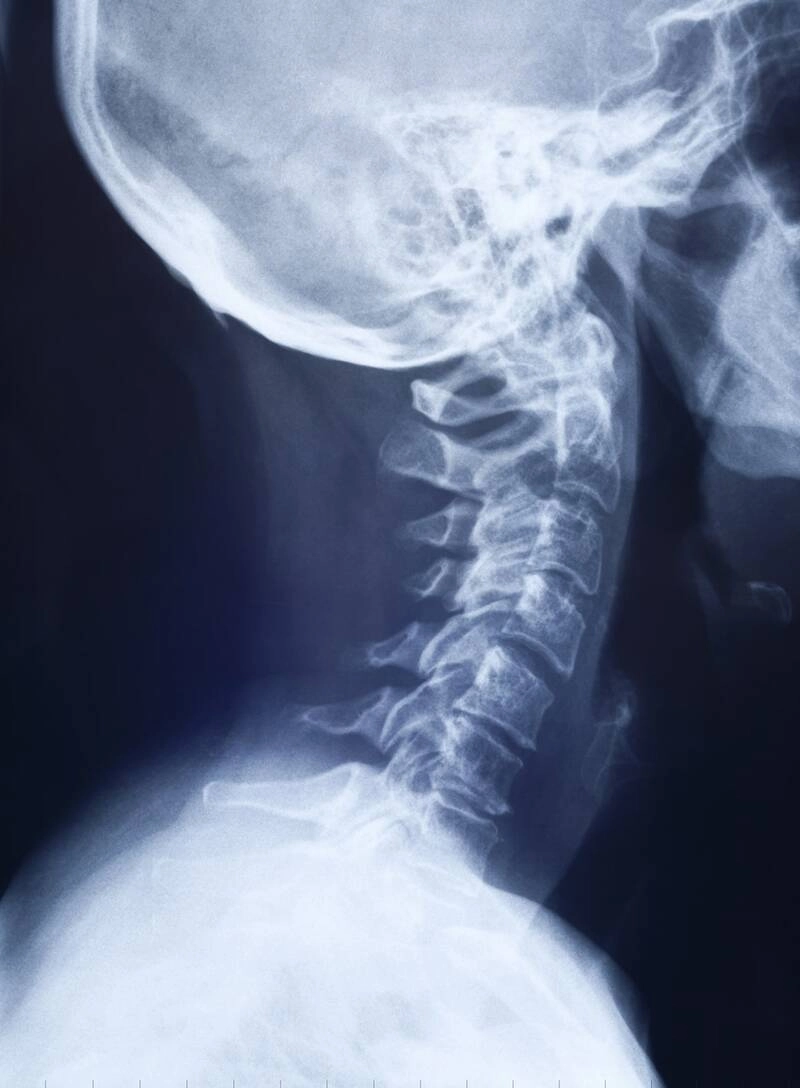

How Does an Anchorage Chiropractor Adjust Your Neck?

Adjustments of the neck, also known as cervical manipulation, is a very precise movement where slight pressure is applied to the neck, almost exclusively done by hand. By adjusting the vertebra in the neck, it improves the mobility of the cervical spine, restores range of motion, offers toxic release after a chiropractic adjustment, and increase the flexibility of the adjoining muscles.

Chiropractic neck adjustment techniques will vary from doctor to doctor and from patient to patient, but most chiropractors based in Anchorage will use flexion distraction, the Logan technique, or a Gonstead adjustment.